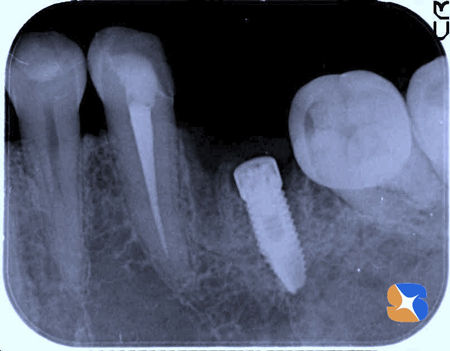

インプラントの手術が終わった直後のレントゲン画像。CTを使って事前の治療計画通り、うまく施術が行われました。

インプラント…スプライン(ジーマー社製)